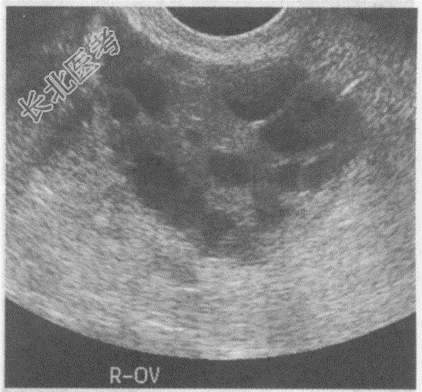

- 单项选择题临床资料:女性患者, 29岁,自述自幼肥胖, 多毛,月经稀少, 结婚5年不孕。

化验检查:雄激素与睾酮升高。

超声综合描述: 经阴道扫查,子宫小, 内膜显示不清;双侧卵巢均匀性增大。包膜光滑增厚回声增强, 每个超声切面可见>10个大小不等无回声区,最大直径0.9cm, 透声清亮。

B、多囊卵巢综合征